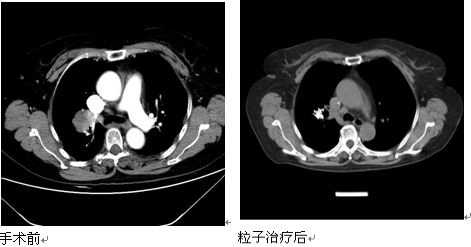

11月23日,一名患晚期肺鳞癌的50岁患者,在鄞州人民医院复查后发现,其40天前经该院呼吸科采用放射性粒子植入技术治疗后,原先5公分大的肿瘤缩小了近一半,更为可喜人的是,原来因肿瘤转移出现的淋巴结肿大也消失了。

这名王姓患者一个月前因持续发热到我院呼吸科就诊。门诊检查中,接诊医生见其血红蛋白明显偏低,将其收治入院。患者入院后,经常规胸片检查,发现王某左侧肺部有一巨大阴影,后经胸部CT和肺活检进一步确检,发现其右肺患有一个5公分大小的鳞癌,且肿瘤内部已经发生溃烂坏死,远处淋巴结出现转移。考虑到患者患的是恶性肿瘤,而且肿瘤已经晚期,错过了手术的机会,加之王某体质又偏弱,恐怕无法耐受化疗,呼吸科在学科带头人,党委书记、副院长俞万钧和科主任彭卫东两位主任医师带领下,经组织科室反复讨论治疗方案,同时通过远程网络与浙江省肿瘤医院的权威专家会诊后,为其制订出实施放射性粒子碘125置入肿瘤的姑息治疗方案。放射性粒子置入手术在放射科CT定位下实施。当天,负责手术的彭卫东主任医师,首先对照肿瘤确定粒子置入的位置,然后将放射性粒子沿定位针放置。术中,王某一直保持清醒状态。手术仅用半个小时,术后3天,王某发热消失后出院。